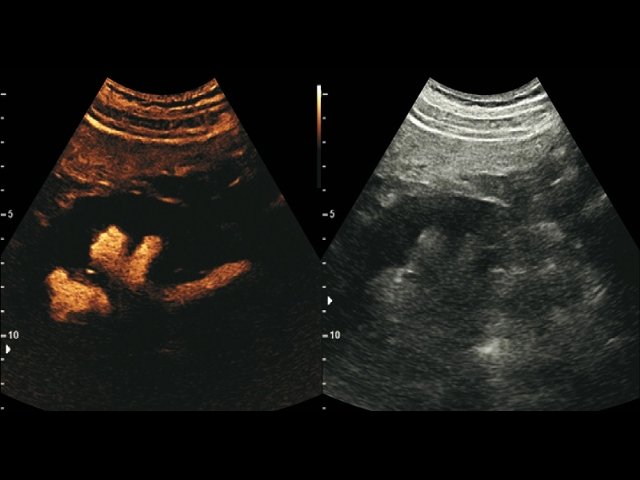

УЗ сканер Samsung HS40

Лидер продаж в высоком классе. Монитор 21,5" высокой четкости, расширенный кардио пакет (Strain+, Stress Echo), экспертные возможности для 3D УЗИ в акушерско-гинекологической практике (STIC, Crystal Vue, 5D Follicle), датчики высокой плотности.